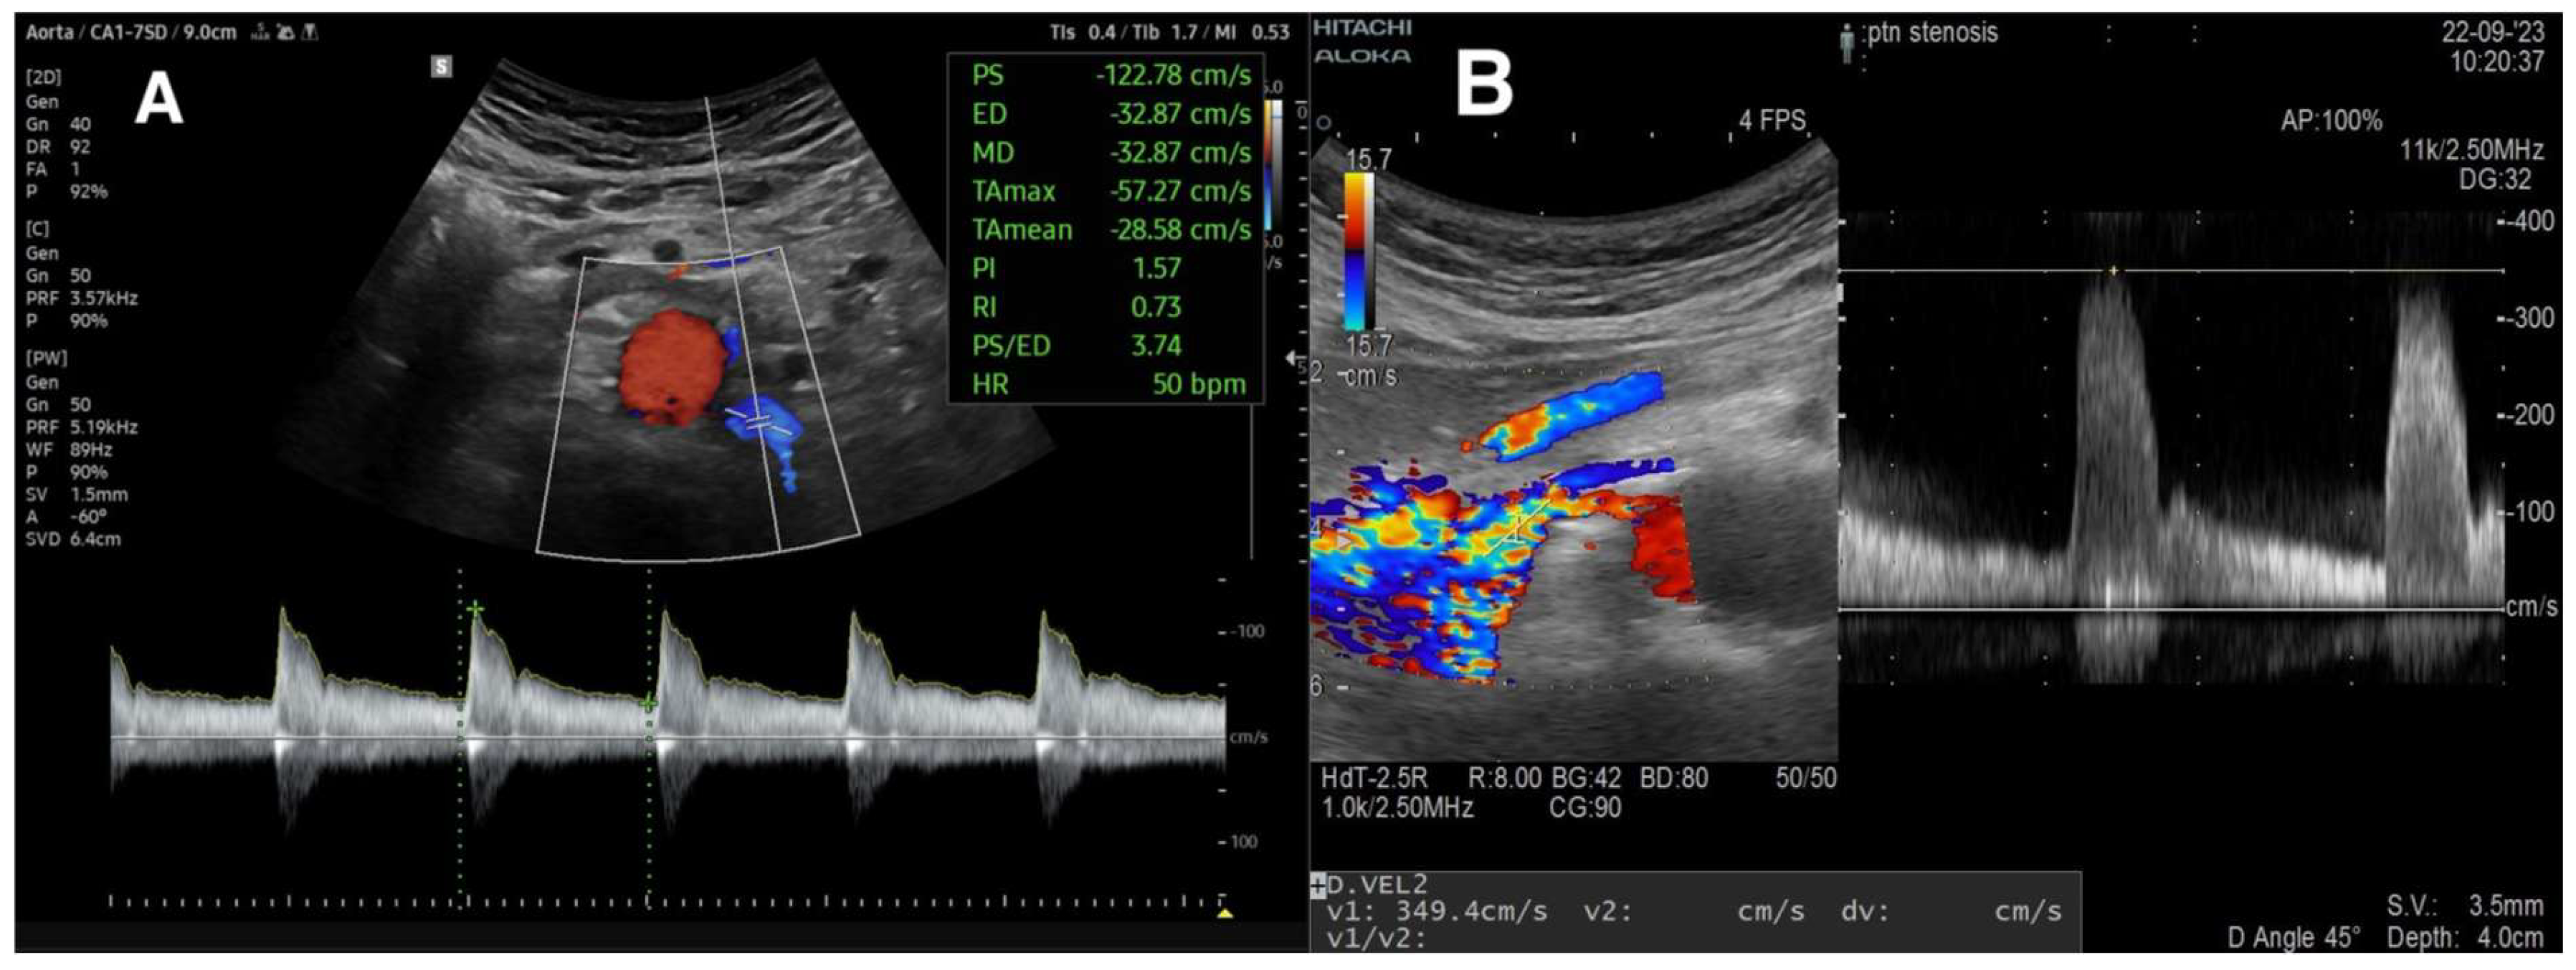

3.2.2. Peak Systolic Velocity and Renal–Aortic Ratio